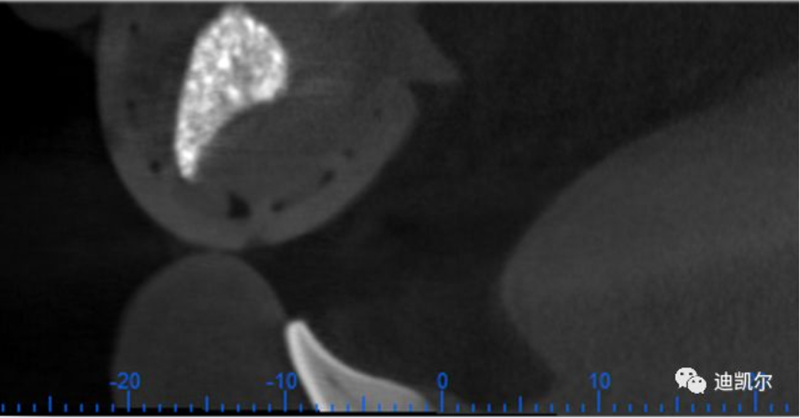

術(shù)前CBCT圖像和測量數(shù)據(jù)

*CBCT顯示骨缺損嚴重,種植窩洞制備困難,種植體很難獲得初期穩(wěn)定性

患者佩戴此U型管開合拍攝CBCT,U型管中的放射標記點清晰顯影